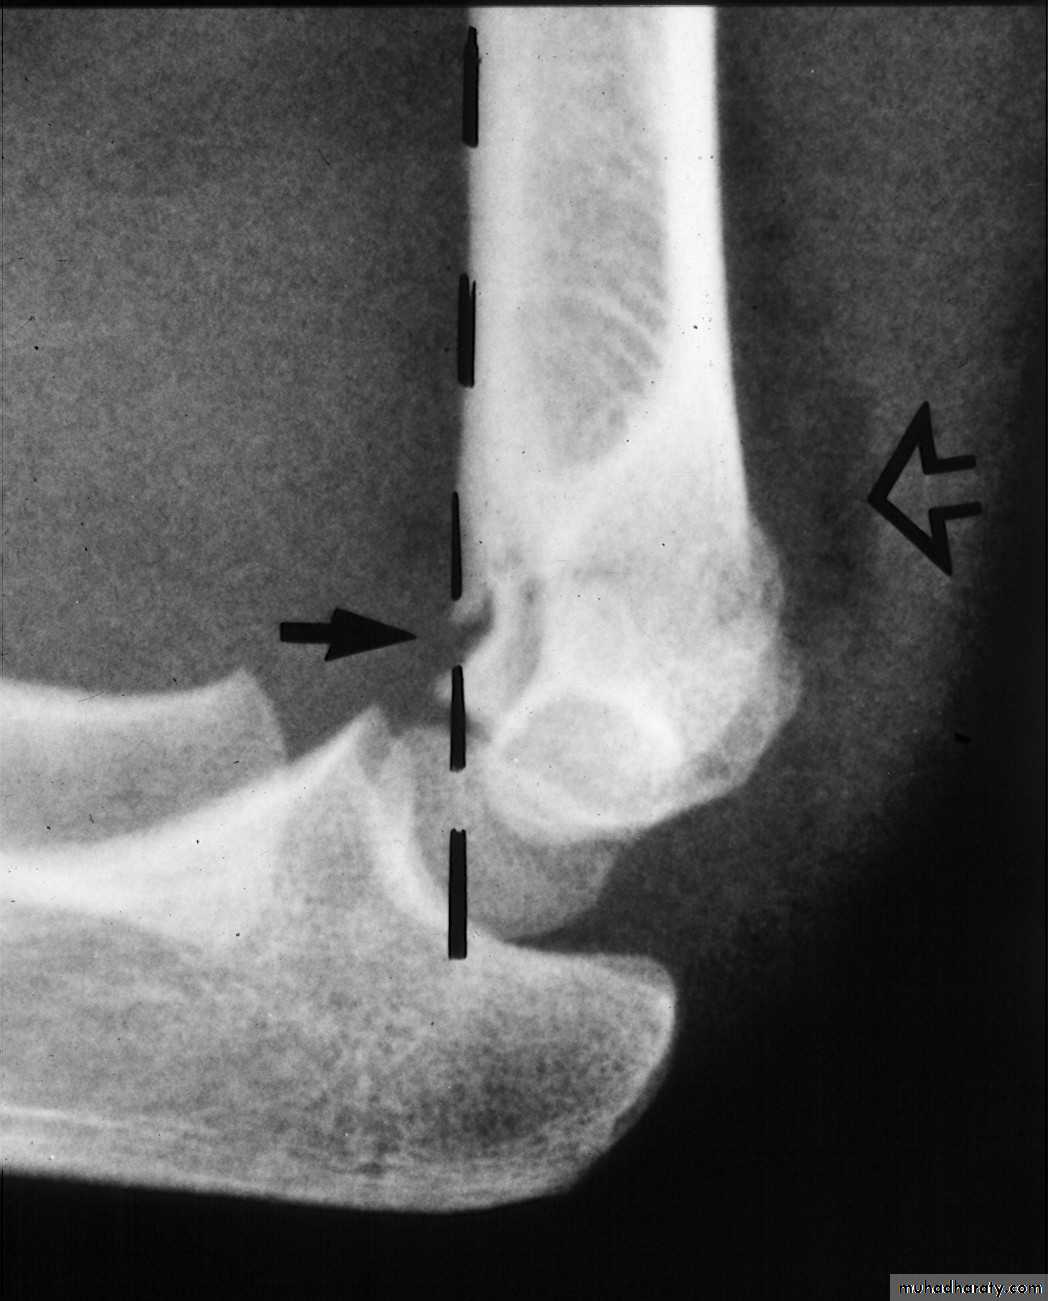

The crescent sign

indicates a varus alignment.

Is there varus?

Is the

crescent sign real?

The anterior

humeral line

barely passes

through the

capitellum.